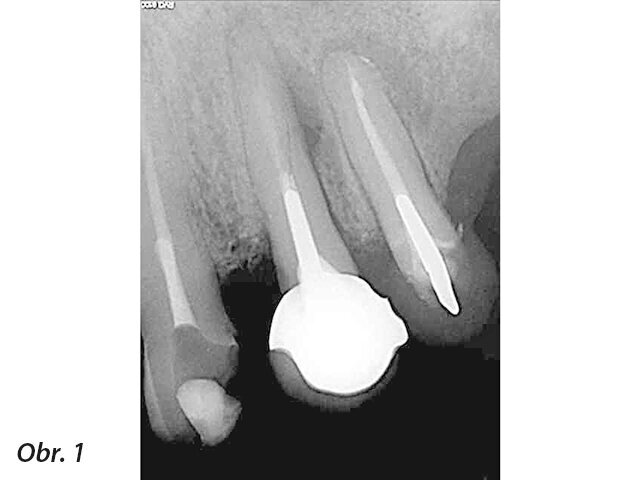

Obecně termín „periapikální léze u implantátu“ (PIL – periapical implant lesion) popisuje radiografický nález kolem apexu implantátu, bez vztahu k dalším periimplantátovým tkáním nebo sousedním zubům. Klinické vyšetření potíží pacienta nemusí vždy indikovat patologický nález, a pokud ano, tak se definice tohoto pojmu překrývá s „retrográdní periimplantitis“ (RPI – retrograde peri-implantitis). RPI má podobnou definici, ale je doprovázeno stížnostmi pacienta a často i klinickými nálezy (obr. 1–3).

RPI manifestuje skrze radiografické a také rozmanité klinické nálezy. V případě RPI je zde přítomna retrográdní infiltrace patologických mikroorganismů, které osídlí apex implantátu. Tato infiltrace často pochází od sousedního zubu, není to ovšem jediná příčina RPI. Další příčiny mají vztah k operačnímu protokolu, protetice a plánování implantace. Ve většině případů vede k diagnóze kombinace více než jednoho faktoru. Laterální defekty, mobilita implantátu a pooperační zánět vztahující se ke zbytku fixtury implantátu nebo zánět periimplantátových tkání jsou z této definice vyloučeny.

Jak PIL, tak RPI se často objeví jako náhodný radiografický nález až léta po zavedení implantátu a protetické rehabilitaci. Pokud jsou doprovázeny klinickými nálezy jako je pozitivní poklep, stížnosti na skus nebo syndrom bolesti, rozlišujeme dvě doby: a) po šesti týdnech od zavedení a b) čtyři až osm týdnů po zatížení. Stížnosti na bolest za delší dobu od zatížení jsou ve většině případů indikací křížové kontaminace od sousedních zubů.